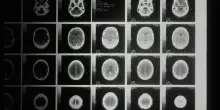

Una nuova terapia cellulare contro il glioblastoma

Il glioblastoma è aggressivo, e difficile da trattare. Un tumore cerebrale per cui esistono ancora poche opzioni terapeutiche. Dall’Istituto …